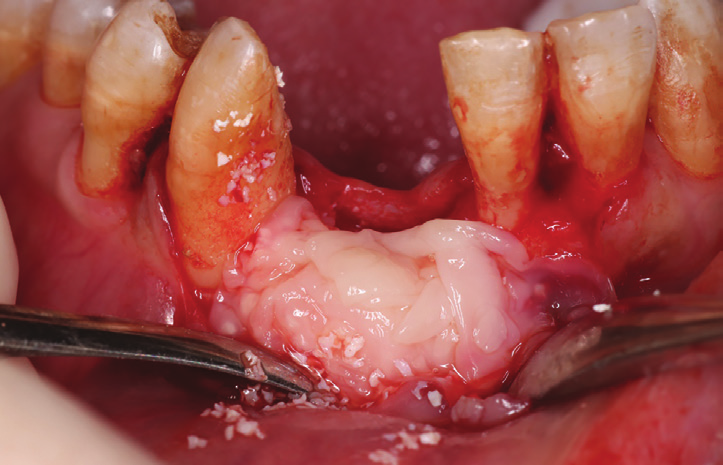

Figure 23: Enucleation of the 1.5 cm lesion followed by extraction of endodontically perforated tooth no 7.

Figure 24: Bone cavity showing extended bone loss.

A 38 years-old female patient came to our clinic with swelling upper anterior area, she was medically fit with no health problems. The patient underwent an orthodontic treatment for 2 years and was about to remove it and place retainer. Intraoral examination showed swelling apical area of tooth no 7. The periapical x-ray and CAT view revealed a lateral perforation on the same mentioned tooth with a well circumscribed radiolucency in apical area (Fig.20, 21). Pain on percussion and slight mobility were noted. A surgical enucleation and extraction of tooth no 7 were conducted (Fig.22, 23, 24). 3 months postoperative CAT view shows an advanced horizontal bone loss with no recurrence of lesion in the area (Fig. 26), clinically after reflection of mucoperiosteal flap, the situation confirmed the CAT image (Fig.25) , the case was planned for PRF -associated bovine bone technique replacing the aggressive autologous bone graft procedure. After collection of PRF from patient blood culture, a first layer of L-PRF covering the bovine bone associated PRF complex (sticky bone) was done (Fig.27). The second layer of L-PRF came to cover the cross-linked collagen membrane (Fig. 28).